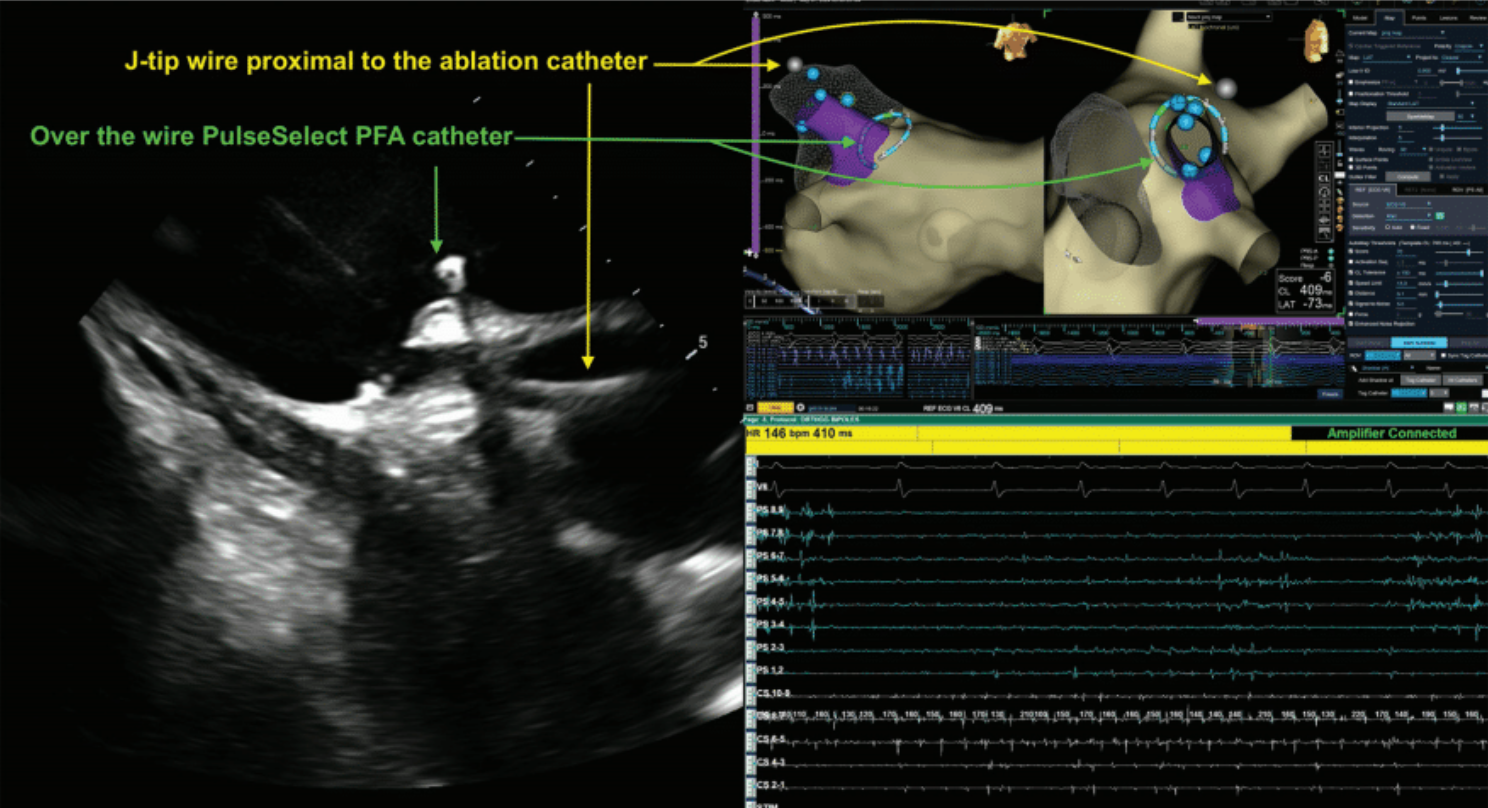

During PFA, the integration of ICE and mapping systems allows for accurate registration of the wire and catheter position within the 3D map, obviating the need for fluoroscopic verification (Figure 7). The map shift is minimal when the coronary sinus catheter is used as a reference for the map. ICE provides real-time, high-resolution visualization of intracardiac structures, enabling precise catheter manipulation and accurate identification of anatomical landmarks. Additionally, the continuous feedback from ICE allows for real-time assessment of adequate catheter contact with the atrial tissue (Figure 8), which is crucial for a successful PFA procedure. The mapping system provides detailed spatial information, enabling the identification and localization of PV ostia, the LA posterior wall, and other critical sites. This spatial precision is crucial in PFA, where lesion sets must be carefully tailored to achieve complete and durable PVI while avoiding gaps that could lead to AF recurrence. The PulseSelect PFA catheter is designed with 20° forward tilted array to ensure contact where the 5th electrode is the first electrode to contact the tissue. Our workflow includes highlighting electrode 5 on our mapping system and tagging it as a lesion once a satisfactory PFA application is delivered. The catheter is then rotated 90° to overlap lesion set and electrode 5 is tagged in its new location. In our stepwise ostial-antral approach, at least 4 ostial and 4 antral applications are applied with electrode 5 tagged at the 12, 3, 6, and 9 o’clock positions in the vein to ensure contiguous PVI (Figure 9).

PulseSelect is an over-the-wire catheter and the wire has to be more distal to the catheter to prevent any arcing with the PulseSelect catheter itself. It is an .032” wire. We connected this wire to our mapping system to visualize the wire on the mapping system, since we are not using fluoroscopy to make sure that the wire is more distal to the catheter. So, we connected to the mapping system and the wire was presented as a dot on the mapping system. We always made sure that the wire was distal to the catheter to prevent arcing. Also, we utilized intracardiac echocardiography (ICE) to ensure contact. We know contact is very important for PFA ablations and ICE helps significantly to ensure contact.